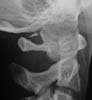

Adolescent. RTA knockdown. ATLS protocols. Put in hard collar. These films below obtained. no neck pain, no swelling, no neurology, no dysaethesia, no previous neck trauma. Closed # tibia.

Lateral

Odontoid

Spot Lateral

I cannot make a diagnosis from these films (which are clearly reproduced, I cannot decipher the information). There is a bony ossicle (?fx fragment) posteriorly between O-C1 and asymmetry of the atlas on open mouth odontoid. I would keep her neck braced and follow the clinical exam; probably with additional studies of the O-C1junction (CT +-MRI) and review with radiologist.

MRI was unremarkable except for showing the bony ossicle. Radiologists said the peg view was rotated.

Our radiologists tell me its part of a congenital arch. I have never seen this kind of remnant at this level. Has anyone else?